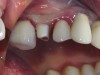

Figure 14. Preoperative photograph of a nonrestorable premolar.

Figure 14